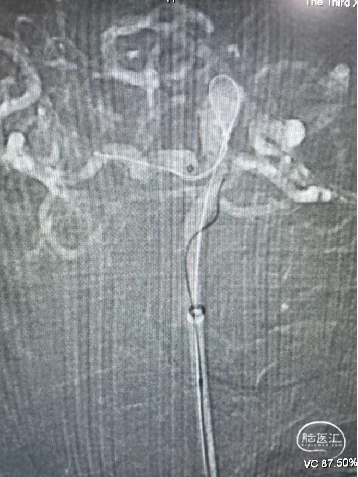

Evolve2.5*2cm支架1个

弹簧圈

XT-27微导管

XT-17微导管

Synchro微导丝

Target弹簧圈Target 7mm*15cm成篮

动脉瘤参数:

动脉瘤大小为6.8*9.7mm,瘤颈宽4mm

载瘤动脉(颈内动脉)近端狭窄处为1.7mm,近端末狭窄处为1.4mm,远端为2.4mm。

支架导管通过困难,支架导管难以达到预定位置。

导丝通过&支架导管到位

释放支架:

支架到位